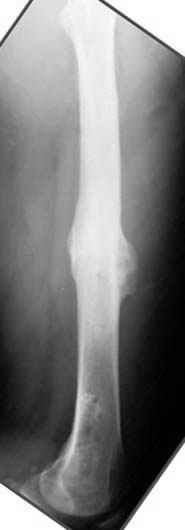

Djoldas Kuldjanov 23 Ноябрь 2004, 18:21

пластическая модель; и коррекция бедра аппаратом Илизарова.

Имею другие снимки тоже, получится как отчет о моей работе.

хотя даже если бы и инфекция , то nail exchange с рассверливанием канала - вариант дебрайдмента) Я думаю, что последовательность развития событий:

Узкий к-м канал - тонкий гвоздь- усталостный перелом дистальных винтов - развитие нестабильности и как ее результат остеолиз вокруг гвоздя - деформация анатомической оси бедра. Похоже, что я понял почему аппарат, а не новый гвоздь:-)

ЕТ - Изначально костно-мозговой канал бедра был узкий, дальнейшее его рассверливание ещё больше скомпрометирует прочность бедра( латеральный кортекс дистального отломка уже истончен), приведет к дефекту наружной стенки - хотя это только мои догадки - хотелось бы знать мнение Джолдаса о выбранной тактике.